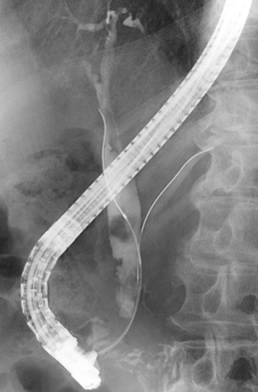

内視鏡的逆行性膵胆管造影

経口的な十二指腸内視鏡下に膵管・胆管内にカテーテルを挿入し、膵管や胆道を造影する検査です。

透視ERCP